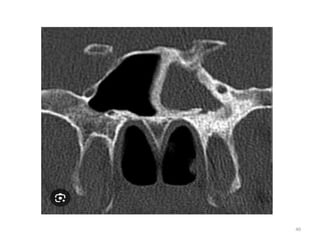

Osteomeatal

complex – coronal

view

• Pathways of communication

• Frontal, ethmoid and maxillary

• 2 key passageways

• Infundibulum

• Middle nasal meatus